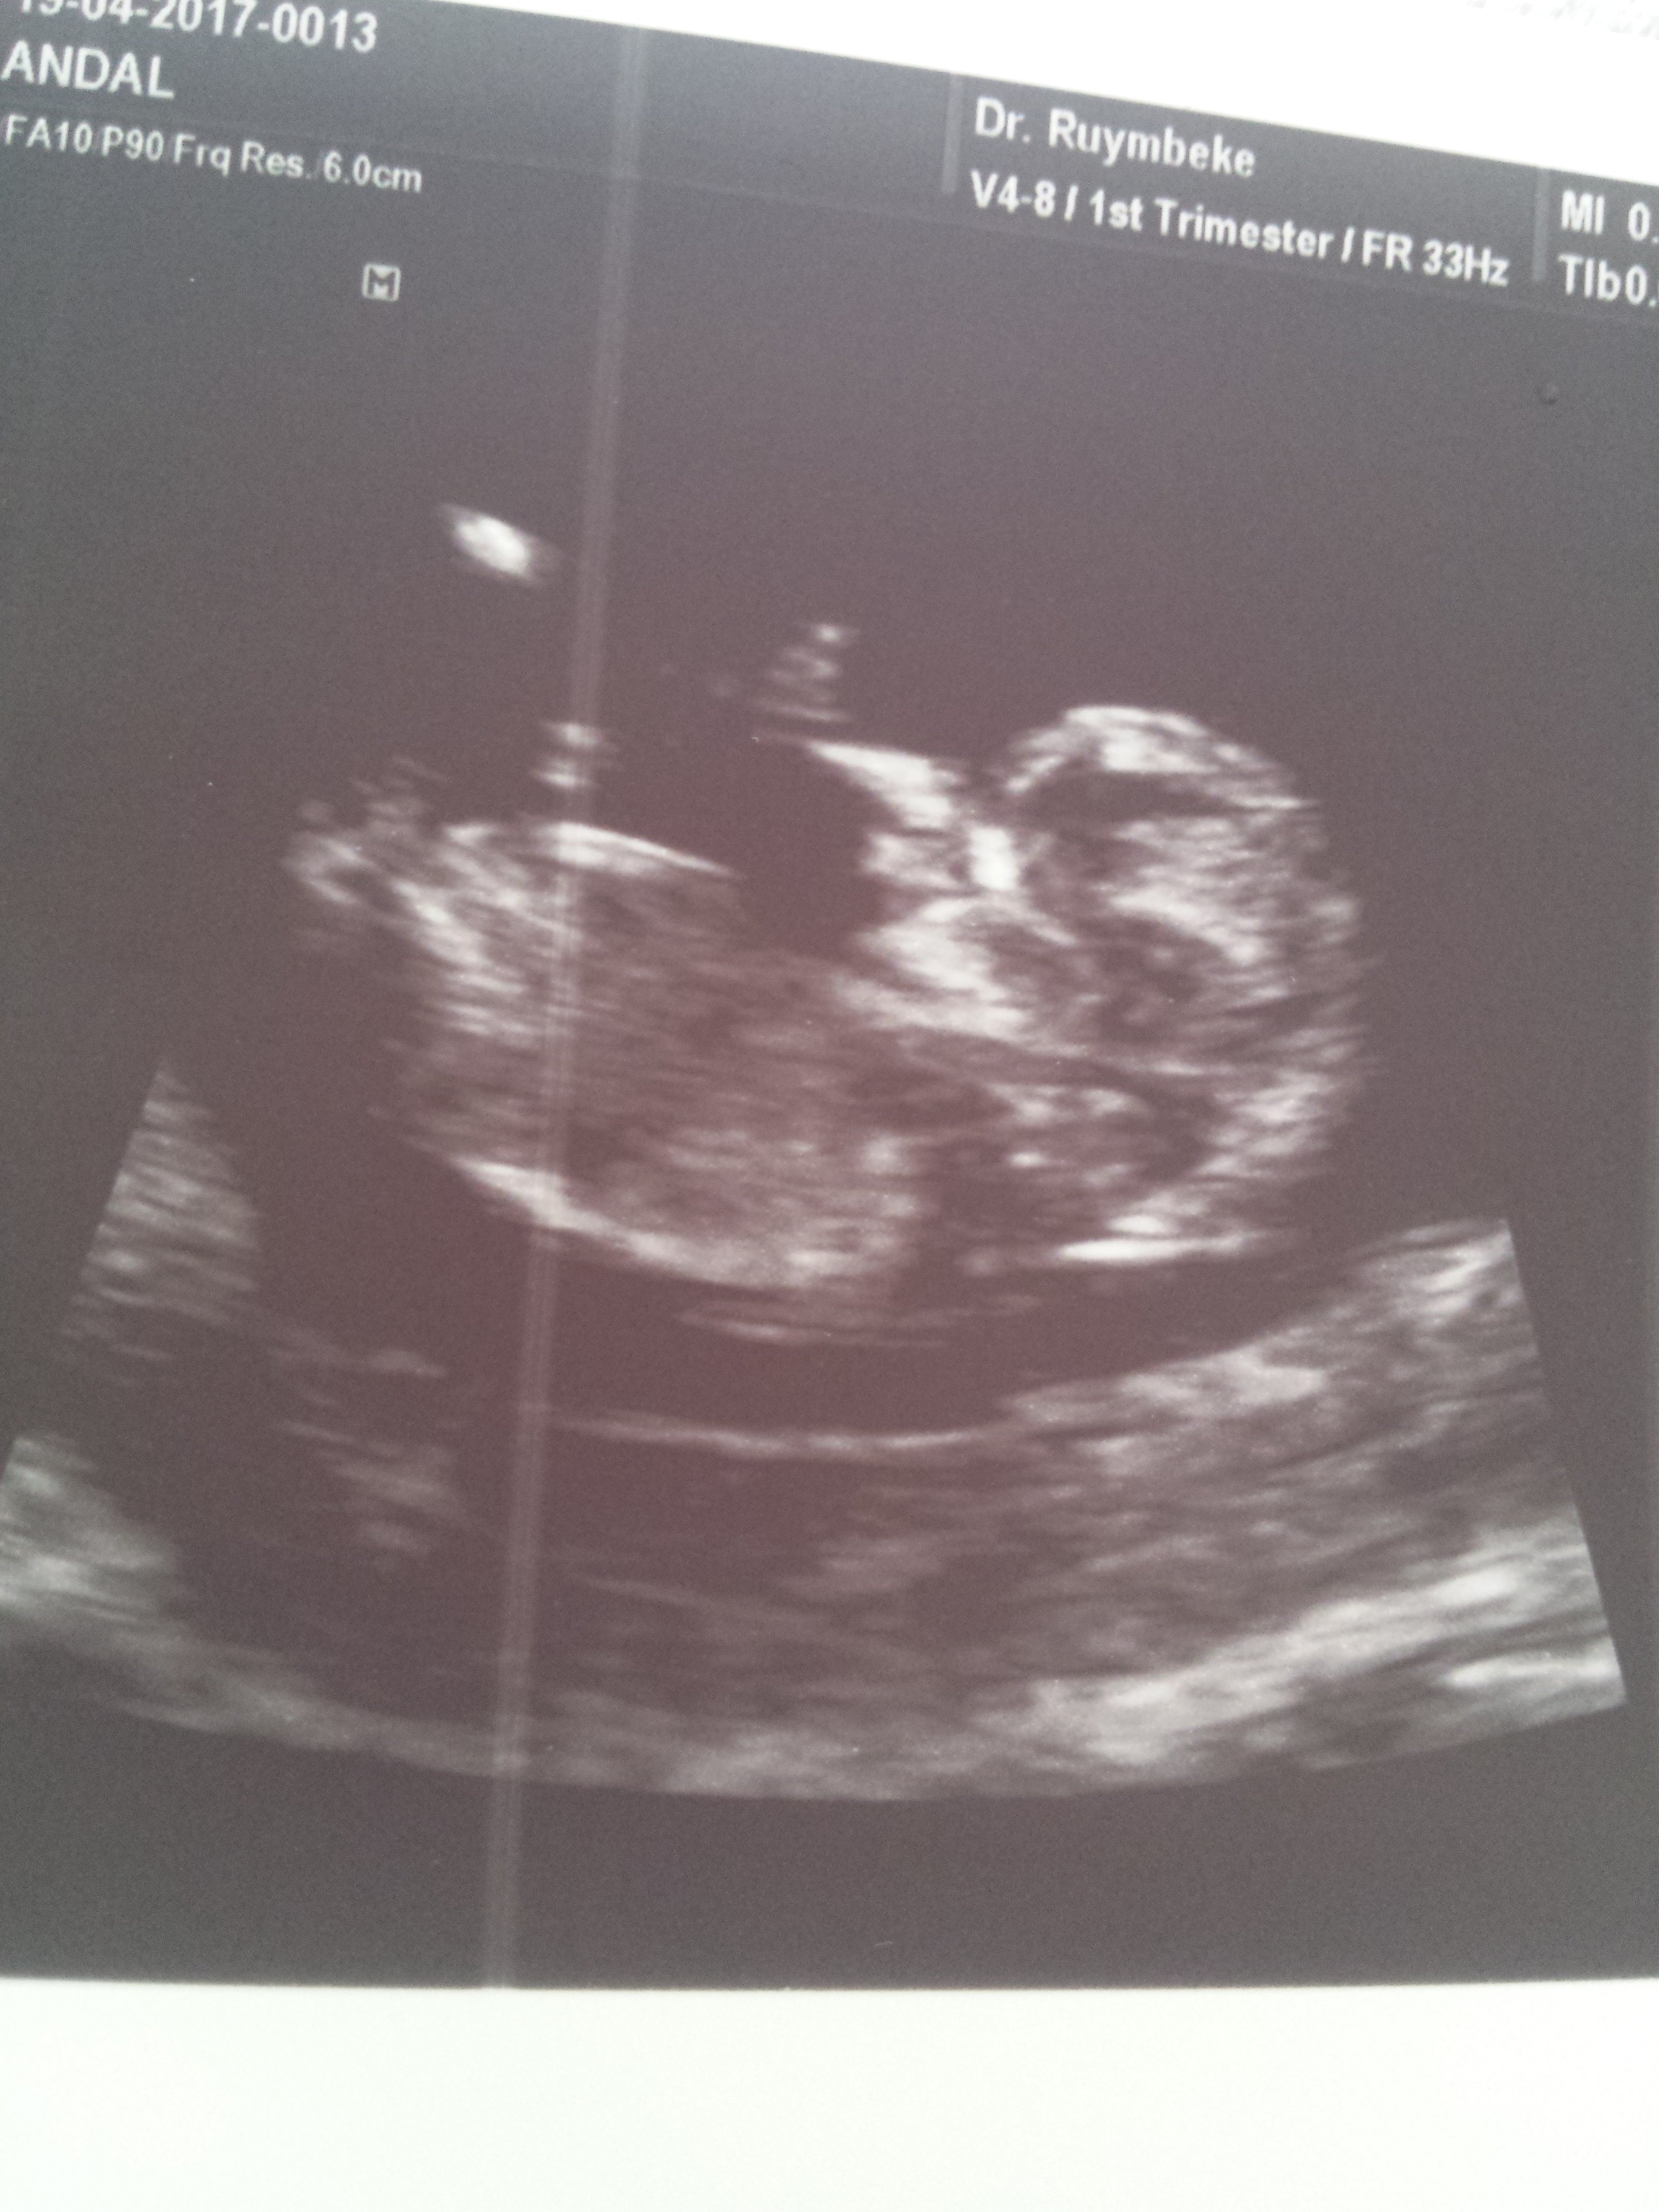

1 1234tmm Yeni Üye Üye 29 Nisan 2017 #266 Ekli dosyayı görüntüle 76265 11+4 dusuncelerinixi alabilirmiyim *BEYZA*' Alıntı: Yorum yaptığınız yerde fotoğraf yükle butonu var.Yüklemeyi ordan yapıcaksınız. Genişletmek için tıkla ... Cok tesekkur canim sanirim oldu.

Uzman SühaN Administrator 29 Nisan 2017 #267 Merhaba, Nub çıkıntısı pek net değil fakat bebeğinizin cinsiyetinin kız olduğunu düşünüyorum.Sağlıklı gebelik geçirmeniz dileği ile.

1 1234tmm Yeni Üye Üye 29 Nisan 2017 #268 *BEYZA*' Alıntı: Merhaba, Nub çıkıntısı pek net değil fakat bebeğinizin cinsiyetinin kız olduğunu düşünüyorum.Sağlıklı gebelik geçirmeniz dileği ile. Genişletmek için tıkla ... Yorumunuz icin tesekkur ederim.eli ayagi duzgun olsun insallah